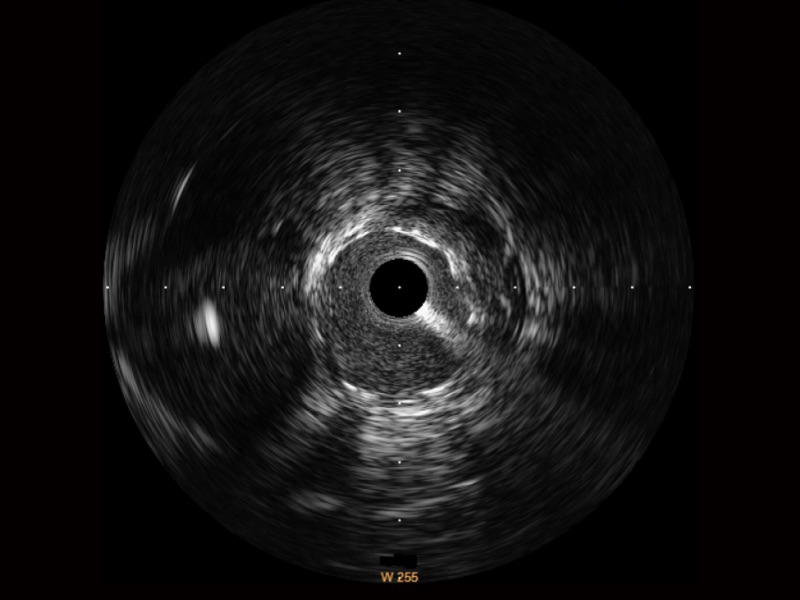

DB中国旗舰官方网站宽频IVUS图像

传统IVUS图像

对比传统IVUS导管成像,DB中国旗舰官方网站宽频IVUS图像的近场支架梁显影更细腻,远场中膜外血管仍清晰可辨,兼顾远中近,兼顾分辨力与穿透深度